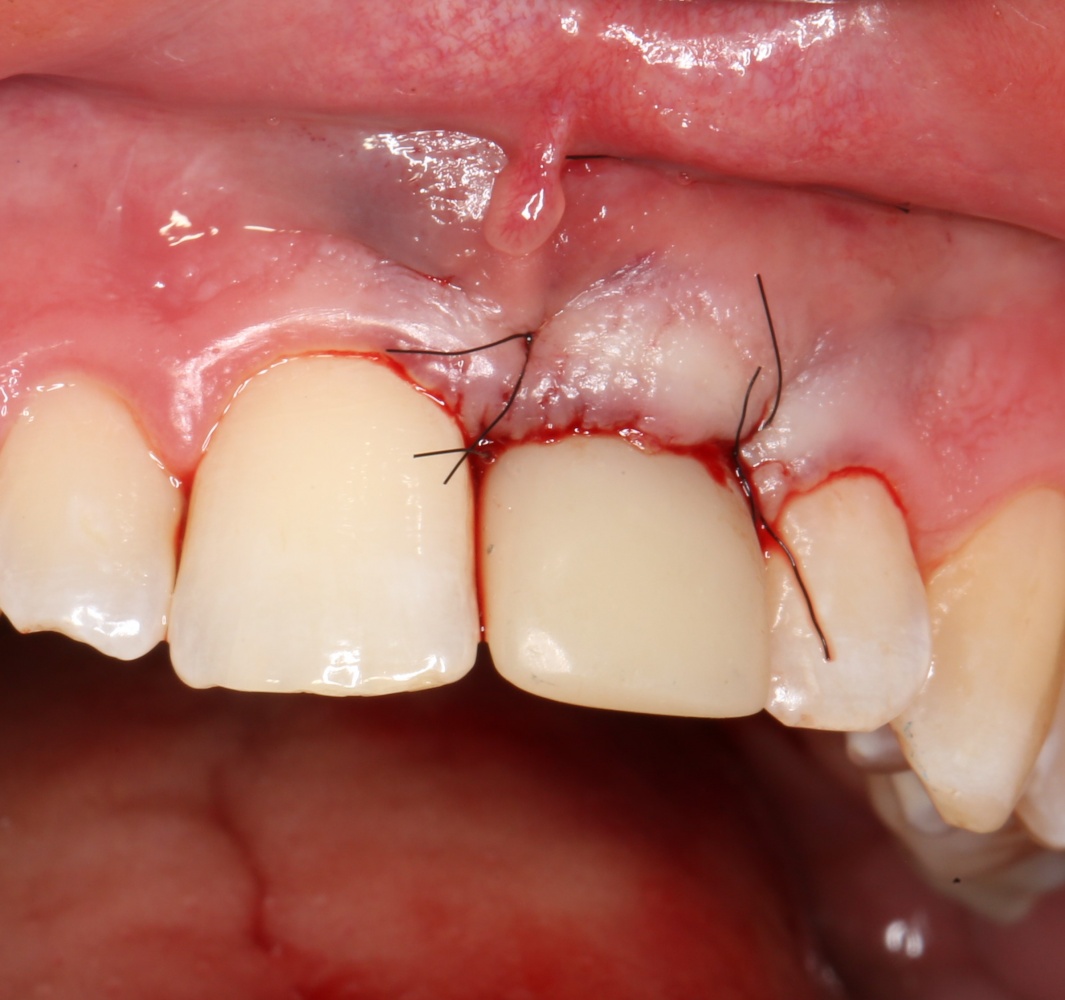

Установка имплантатов

По ряду уже упомянутых выше причин, для решения этой клинической задачи мы выбрали имплантаты Xive. Лунки для них мы уже приготовили. возможную первичную стабильность оценили. Имплантаты мы установили с усилием чуть больше 15-20 Нсм — такого крутящего момента более, чем достаточно, особенно если учесть, что временные коронки будут соединяться между собой.

Подробно о том, что такое крутящий момент и хирургический протокол можно прочитать здесь>> и тут>>, соответственно. Из-за использования специальных индивидуализируемых временных абатментов, имеющих только три положения, нам нужно позиционировать платформу имплантатов по граням. Это очень просто  — мы выводим вырез абатмента TempBase (он входит в комплект поставки) вестибулярно.

После перкуторной проверки стабильности имплантатов и точности позиционирования, мы переходим к следующему этапу — сохранению десневого контура.

Установка имплантатов занимает около двух минут.